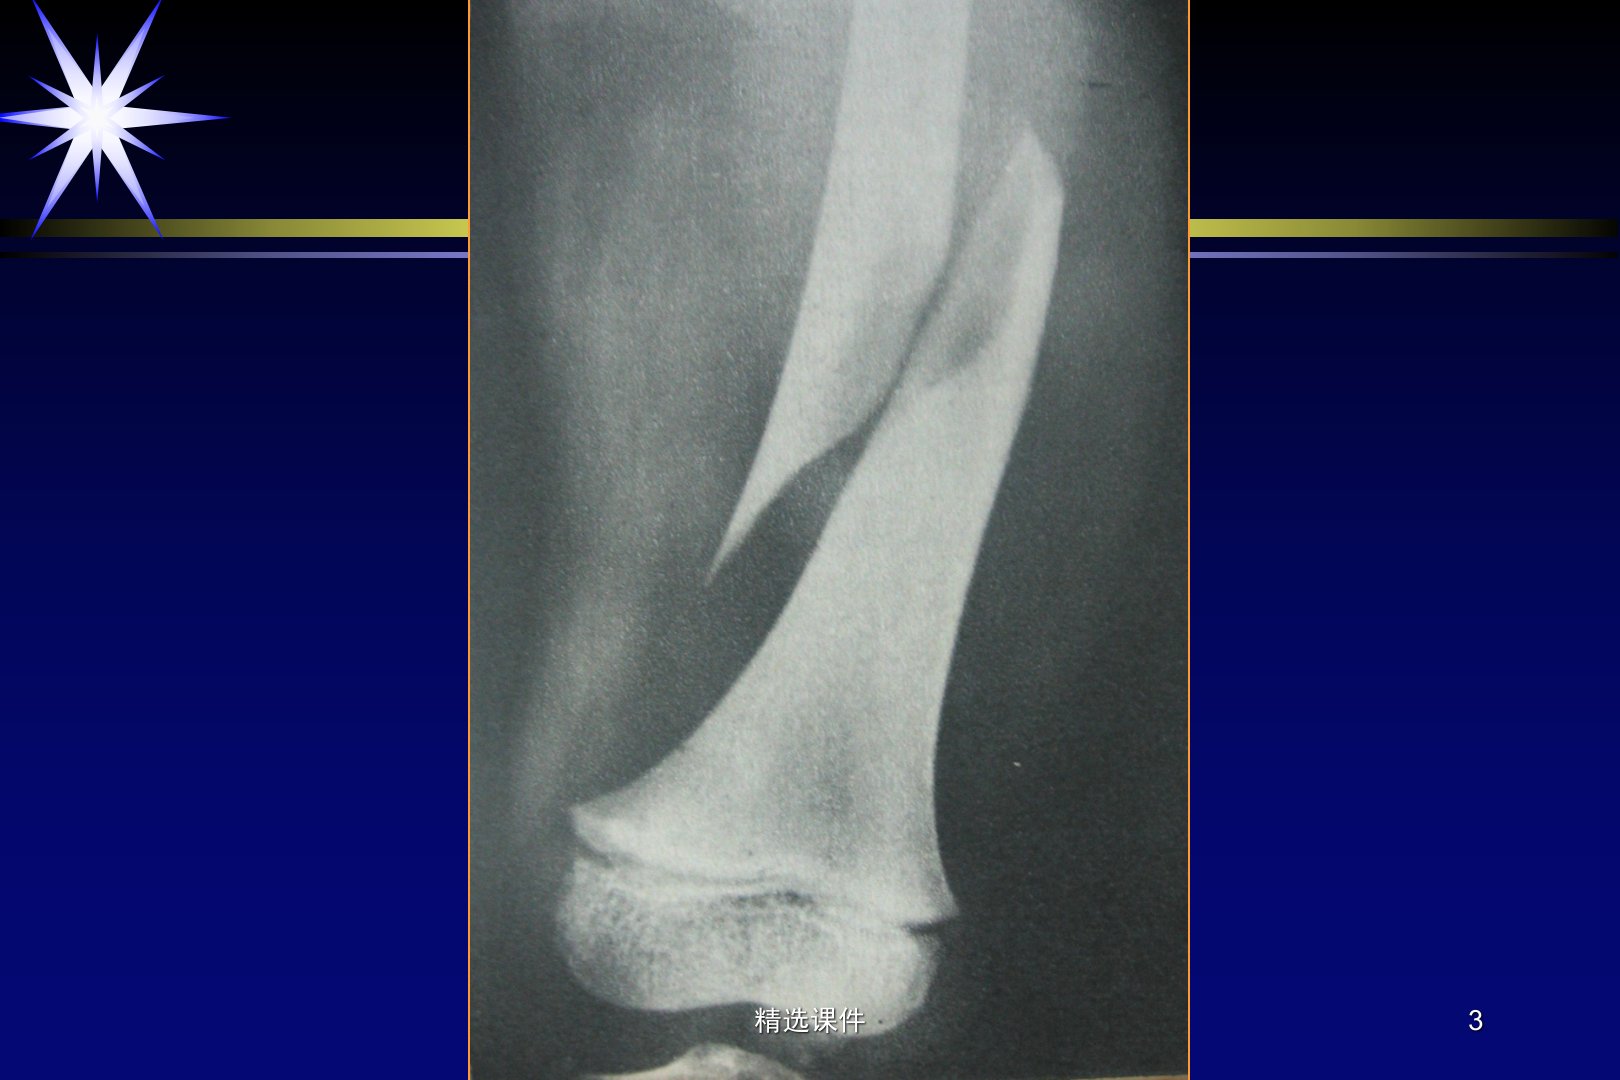

第四章聚焦骨与关节创伤。骨关节损伤常见于日常劳动、生活中的意外及战伤。骨折指骨结构完整性和连续性的中断原因包括直接暴力、传递暴力、体内异常力量作用等。X线检查可明确有无骨折、了解骨折详情为治疗提供参考。骨折类型多样可按原因分为外伤性、疲劳性、病理性;按皮肤完整与否分为开放性、闭合性;按程度和形态分为不完全性、完全性;按复位后稳定程度分为稳定性、不稳定性。儿童骨折有骨骺分离和青枝骨折特点疲劳骨折则是持续外力或长期积累性损伤的慢性骨折。骨折愈合分肉芽组织修复期、骨痂形成期、骨痂连接期、骨痂塑形期。骨折并发症和后遗症包括延迟愈合或不愈合、骨关节感染、缺血性坏死、畸形愈合、创伤性骨关节病、神经和血管损伤等。脱位是构成关节诸骨对应关系的脱离、错位分创伤性、病理性、先天性。